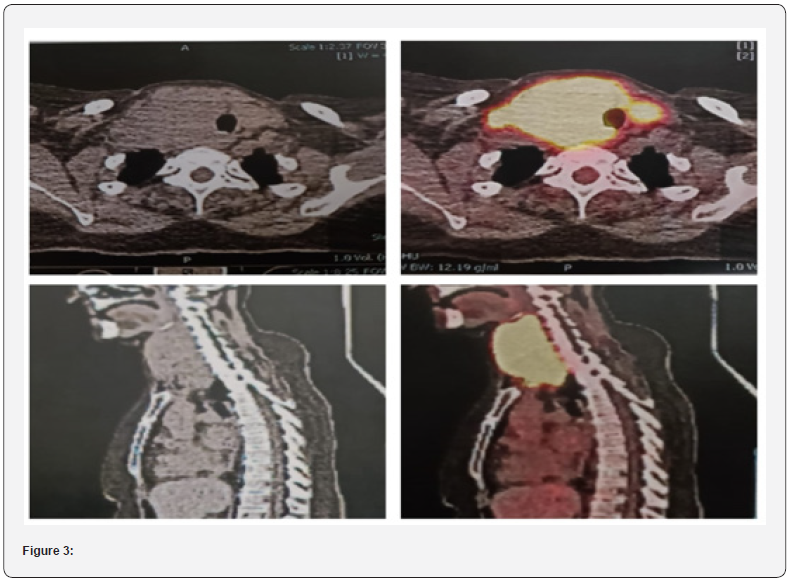

Pet Scan 18/10/23

Head and Neck: There is evidence of normal FDG distribution

over the brain cortex with no evidence of mass effect but some

misregistration artifact. Para-nasal sinuses are clear. A large

hypermetabolic confluent mass involving right lobe of thyroid and

pushing the tracheal towards left, crossing midline and involving

left lobe. The mass extends inferiorly to suprasternal notch and

superiorly to right pyriform sinus. Mass is abutting the right

lamina of thyroid cartilage. Mass is measuring 60 x 80 x 104 mm

(TR x APx CC) and SUV smax 2.4.0 on right (57 x 72 x 95 mm in last

CT) and 26 x23mm and SUV max 14.9 on left lobe. Hypermetabolic

nodes are seen in right cervical lev

el II region (largest measuring

13 x 10 mm and SUV max 8.4).

Chest: Both breasts show no evidence of hypermetabolic

focus. No evidence of hypermetabolic node in axilla, hilar or

mediastinal regions. A tiny calcified granuloma is seen lower lobe

of right lung. Rest of the structure in chest shows physiological

tracer distribution with normal morphology. There is no evidence

of pulmonary nodules on FDG or CT images.

Abdomen And Pelvis: Uniform tracer distribution is seen

over liver (172 mm CC) and sp. (120 mm CC). A tiny radiopaque

gallstone is seen. No evidence of hypermetabolic nodes in

abdomen or pelvic region is noted. Both adrenals and pancreas

are within normal limits. Physiological tracer distribution is seen

in bowel and urinary tract.

Skeletal: Mild scoliotic deformity is seen involving lumbar

spine with age-related degenerative arthritis changes. No

evidence of FDG avid marrow or skeletal metastasis.

Lugano Classification: Stage I-E